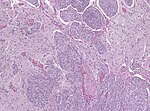

Microscopic

Features (memory device WCN):

- Whorled appearance - key feature.

- Calcification, psammomatous (target-like appearance; (tight) onion skin).

- +/-Nuclear pseudoinclusions - focal nuclear clearing with a sharp interface to unremarkable chromatin.

Meningothelial meningioma

- Most common.

Microscopic:

- Syncytial, nuclear clearing (pseudoinclusions).

- Whorls, Onion bulb formations.

- Few psammoma bodies.